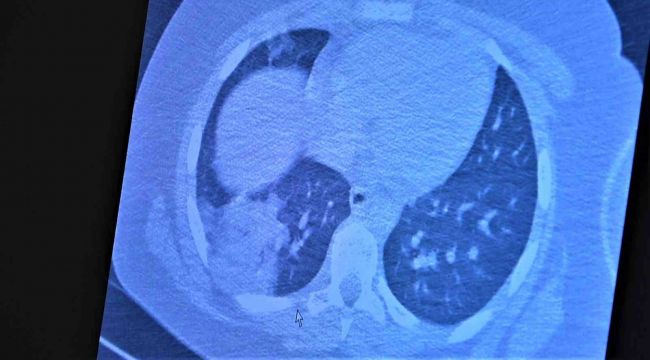

Korona virüsün mutasyona uğramış hali artık aşısız çocuklara ciddi zararlar vermeye başladığına dikkat çeken Göğüs Hastalıkları Uzm. Prof. Dr. Özkaya, 11 ve 14 yaşlarındaki koronaya yakalanmış ve ciddi akciğer tutulumlarıyla tedavi gören çocukların akciğer tomografilerini gözler önüne serdi.

Çocukların akciğer tomografilerini inceleyen Özkaya, "11 yaşında kovid pozitif bir öğrencimiz, yüksek ateş ve nefes darlığı ile bize geldi. Ciddi akciğer tutulumu var. Geçen yıl 'bu çocuklar hastalıktan etkilenmiyor' diyorduk. Bu çocukta görüyorsunuz buzlu camlar ve konsolidasyon alanlarla seyrediyor. Geçen yıl bu şekilde çok çocuk görmüyorduk. Önümüzdeki aylarda bu şekilde devam ederse çocuklarımızı kaybetmeye bile başlayabiliriz. 14 yaşında pozitif olan bir diğer çocuğumuz ise aşı randevusu almış ama aşısını olmadan ateş ve öksürükle başvurdu. Halen şanslıyız. Çocuklar tedaviye çok hızlı yanıt veriyor.  Çekilen tomografisinde ise bilaterel yaygın tutulumları vardı. Bu ise 24 yaşında genç hastanın akciğer tomografisi. Bu kişide yaygın akciğer tutulumları görüldü. Bunu da tedavi ettik. Önümüzdeki aylarda ne getirecek ne götürecek beraber göreceğiz. Özellikle havaların soğumasıyla kapalı ortamlarda geçirilen zamanın ve kalabalıkların etkisiyle vaka sayılarının önümüzdeki günlerde artacağını biliyoruz. Şu an hastalık gerçekten 30-40 yaş altı gençlerde görülmeye başladı. Poliklinik şartlarında olanların büyük bir kısmı 30 yaş altı hastalar. Servislerde yatanlarda orta yaş ve altı nüfus. Yoğun bakımda yatanların büyük bir kısmı ise aşısız erişkin insanlardan oluşuyor" diye konuştu.